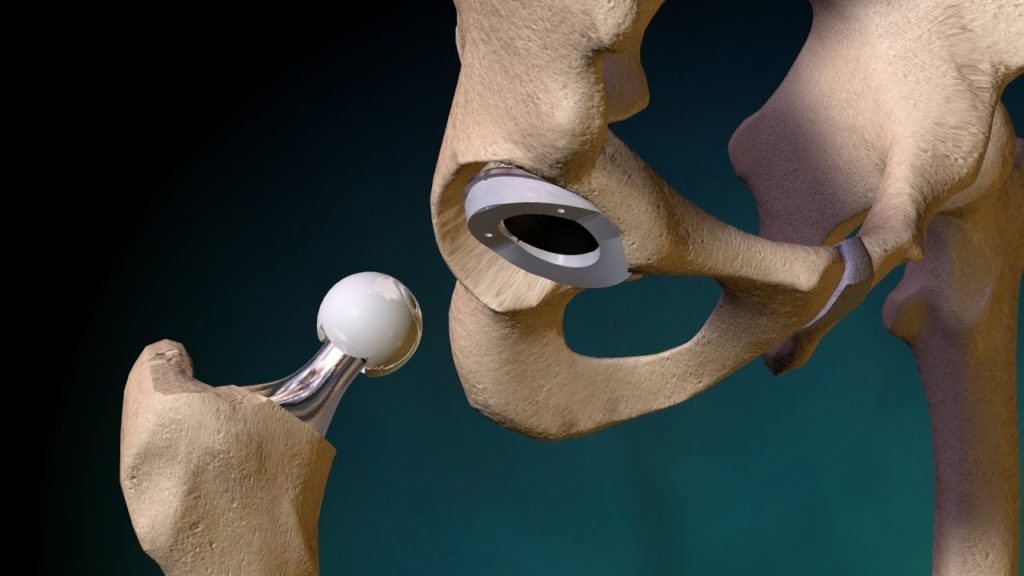

يصاب بعض الأشخاص بالتهاب مزمن في مفصل الورك، ما يؤدي إلى إعاقة الحركة والمشي، وفي هذه الحالة ينصح الأطباء بإجراء عملية جراحية لاستبدال الورك بآخر صناعي حتى يتمكن المريض من العودة إلى الحركة بسهولة وتخفيف الألم.

إجراء استبدال مفصل الورك، سيقوم الجراح بما يلي:

– عمل شق فوق الجهة الأمامية أو الجانبية للورك، وعبر طبقات الأنسجة.

– إزالة العظام والغضاريف المريضة والتالفة، وترك العظام السليمة في مكانها.

– زراعة تجويف المفصل الصناعي في عظم الحوض، لاستبدال التجويف التالف.

– استبدال الجزء العلوي المستدير من الفخذ بالكرة الصناعية، والتي يتم وصلها بساق يتم تثبيتها داخل عظمة الفخذ.

وما زالت تقنيات استبدال مفصل الورك في تطور مستمر، ومع مواصلة الجراحين لابتكار تقنيات جراحية أقل تدخلا، فهناك أمل في أن تقلل تلك التقنيات من الألم والوقت اللازم للشفاء مقارنة بجراحات استبدال مفصل الورك العادية.

ولكن أظهرت الدراسات التي تقارن بين نتائج الجراحات العادية لاستبدال مفصل الورك وتلك الأقل تدخلا نتائج متضاربة.